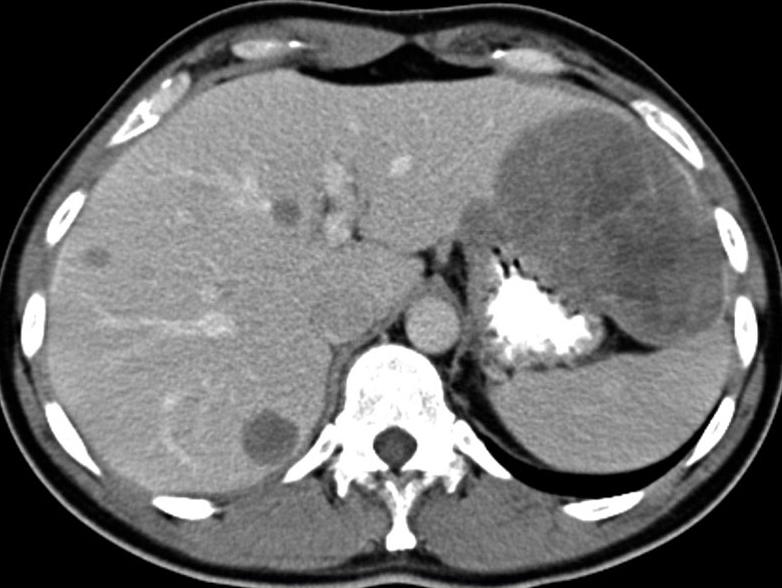

| Extension metastasique

hepatique et peritoneale d'une tumeur de GIST . Des

masse a hypo-dense intra hepatique . TDM en coupe

axiale |

Tumeur de GIST

polylobulaire de jejunum avec nodule metastasique du

foie droit ( extension metastasique hepatique ) |